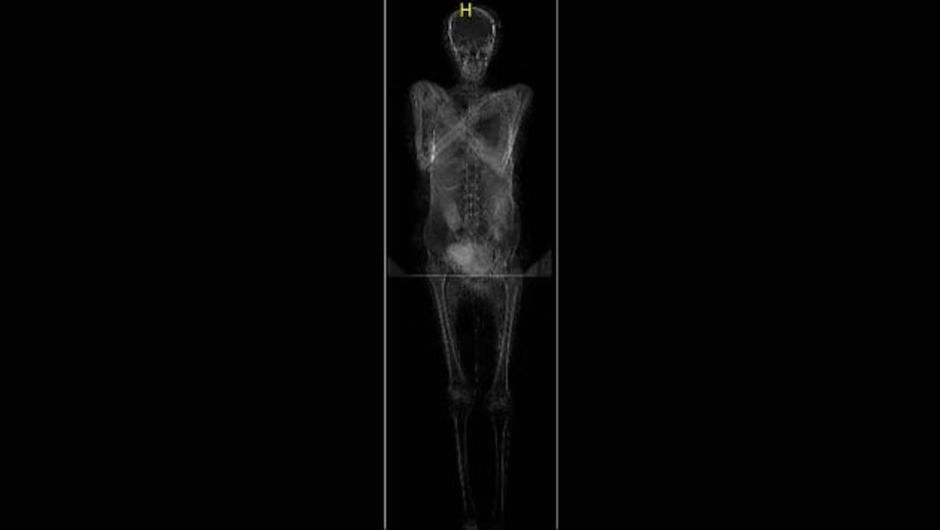

La momia embarazada

En abril de este año los científicos no pudieron ocultar su sorpresa al descubrir la primera momia embarazada. Es la primera momia de este tipo detectada en el mundo.

Quienes realizaron el descubrimiento fueron un grupo de científicos que estudian las momias del Museo Nacional de Varsovia. Marzena Ozarek-Szilke, antropóloga y arqueóloga de la Facultad de Arqueología de la Universidad de Varsovia explicó que estaban por cerrar su investigación cuando vieron imágenes que los impactaron.

"Con mi esposo Stanislaw, un arqueólogo de Egipto, pudimos ver las imágenes por última vez y notamos una imagen familiar de padres de tres niños en el abdomen de la mujer fallecida: un pie diminuto", explicó.